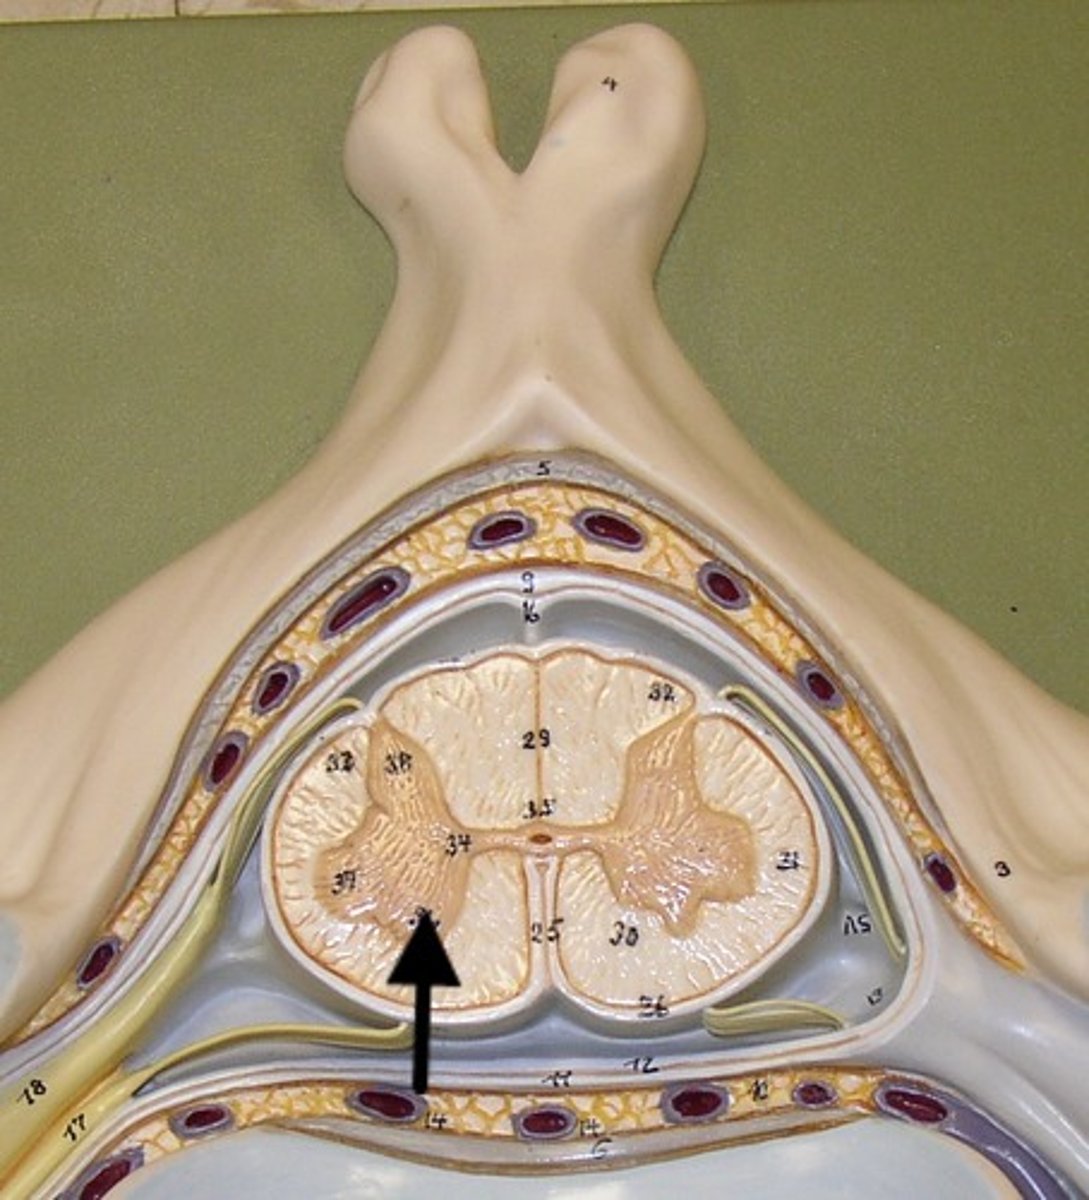

Spinal cord Anatomy (cross-sectional)

1)Internal butterfly shaped gray matter,

2)Exterior white matter,

3)Central canal filled with cerebrospinal fluid (CSF),

4)Cushioned & protected by meninges,

5)Pia mater,

6)Spinal nerves leave at the level of each vertenrae

Horns of Spinal Cord Anatomy

Dorsal Horns,

Ventral Horns,

Lateral Horns

Dorsal Horns

Lateral Horns

Ventral Horns

Interneurons

exterior white matter of the spinal cord

Ascending (sensory) and descending (motor) myelinated nerve tracts,

Posterior, anterior, lateral columns or funiculi

Posterior Columns

Anterior Columns

Lateral Columns/ funiculi

Central canal filled with what?

Central canal filled with cerebrospinal fluid (CSF)

Cushioned and protected by meninges

1) Cover the spinal cord

2) Dura mater, Arachnoid & Pia mater

dura mater of spinal cord

1) Separated from the periosteum by the epidermal space (fat, blood vessels)

2) Subdural space between dura and arachnoid mater

Dura Mater